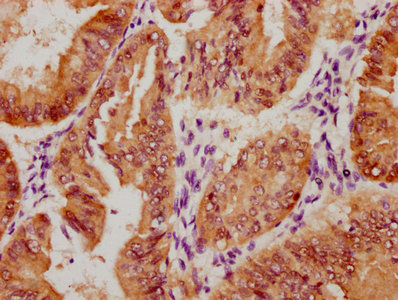

The image on the left is immunohistochemistry of paraffin-embedded Human thyroid cancer tissue using CSB-PA274333(DKK3 Antibody) at dilution 1/30, on the right is treated with fusion protein. (Original magnification: ×200)

The image on the left is immunohistochemistry of paraffin-embedded Human gastric cancer tissue using CSB-PA274333(DKK3 Antibody) at dilution 1/30, on the right is treated with fusion protein. (Original magnification: ×200)